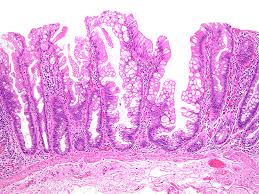

대장 선종은 일반적으로 대장 내벽에서 발생하는 비정상적인 세포 성장으로, 이는 대부분 양성입니다. 그러나 일부 유형의 선종은 악성 변화를 일으킬 수 있는 가능성이 있습니다. 대장 선종은 크게 다음과 같은 종류로 분류할 수 있습니다:

- 타입 1: 선종 - 이 유형은 가장 일반적이며, 세포 구조가 비정상적으로 변화되는 것이 특징입니다. 이들은 대개 작고, 대장 점막 위에 튀어나온 형태로 나타납니다. 대부분은 종양이 아닌 비후성 변화입니다.

- 타입 2: 위선종 - 이 유형은 선의 구조가 더 복잡해지며, 대장암으로 발전할 가능성이 높아집니다. 이들은 비교적 큰 크기로 성장하며, 정기적인 검사가 필요합니다.

- 타입 3: 선종성 대장 용종 - 이 유형은 가장 위험한 것으로, 암으로 발전할 가능성이 큽니다. 조기 발견과 제거가 필요한 이유입니다.

대장 선종은 대개 대장 내시경 검사 시 발견되며, 그 크기와 형태에 따라 필요 시 생검이 진행될 수 있습니다. 이러한 검사들은 조기 발견과 예방 조치에 중요한 역할을 합니다. 따라서 정기적인 검진이 매우 중요합니다.